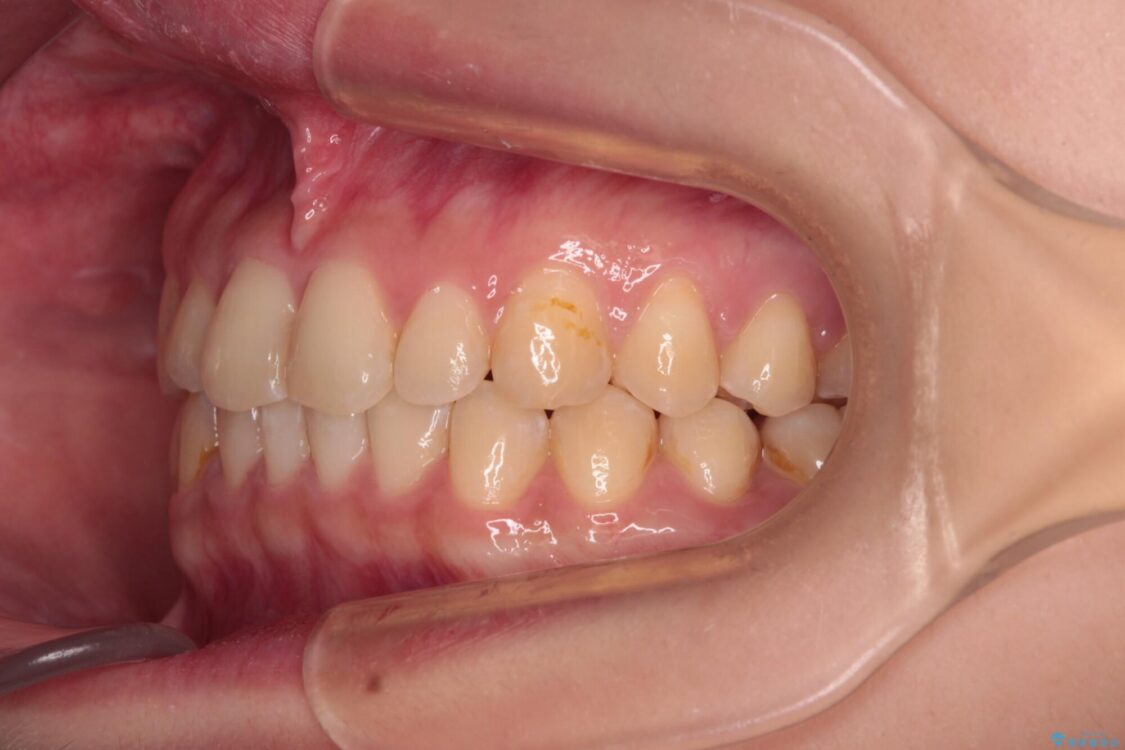

治療前

• 治療途中の奥歯と矯正治療の後戻り インビザライン・ライトによる矯正治療 治療前画像

根管治療を行ったままの奥歯と、矯正治療の後戻りを気にして来院された患者様です。

治療計画

根管治療された歯に症状はなく、オールセラミッククラウンにて補綴治療を行うこととしました。

矯正治療の後戻りは軽微であったため、インビザラインの簡易パッケージであるインビザライン・ライトを用いて歯列を整えることとしました。